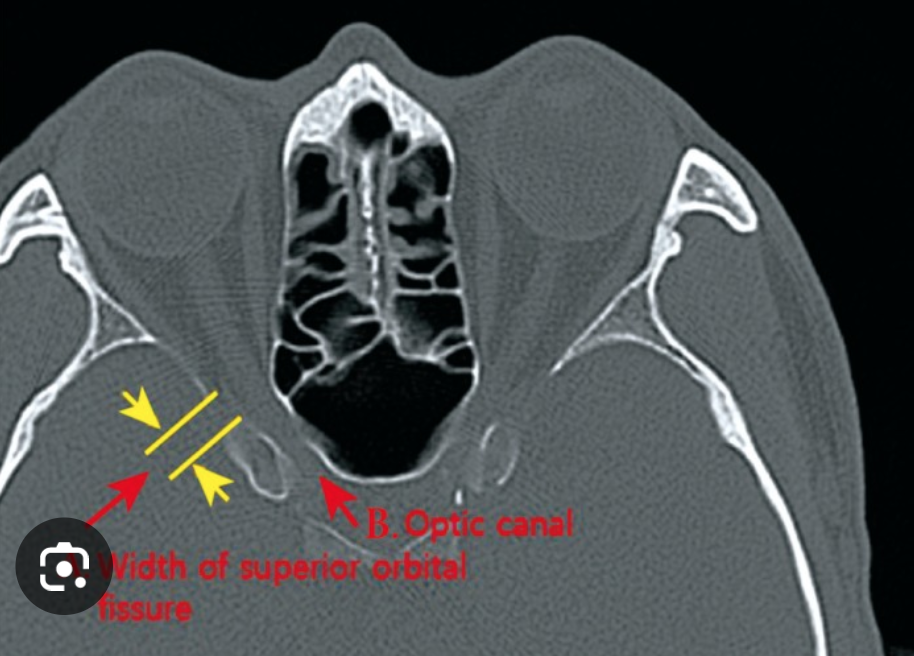

Optic Canal

• Structures passing through here:

• CN 1

• Ophthalmic artery

Superior Orbital Fissure

• CN 3, 4, 5-V1, 6

• Superior ophthalmic vein